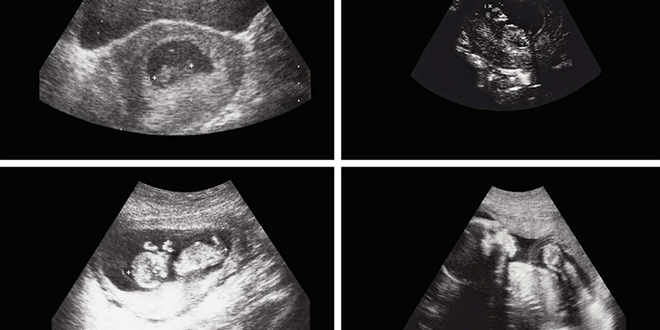

وبعد إجراء الفحوصات بالأشعة، اكتشف الأطباء أن التكوين في تجويف بطن الرضيع يحتوي على “أنسجة رخوة ودهون وسوائل إضافة إلى بنية عظمية واضحة” ما دفعهم إلى الاشتباه في وجود جنين داخل جسده.

وتمكن الفريق الطبي من استخراج الجنين، الذي بلغ حجمه حوالي “8×12” سنتيمتراً، في عملية استغرقت عدة ساعات، وأشرف عليها فريق من الجراحين الأفغان.